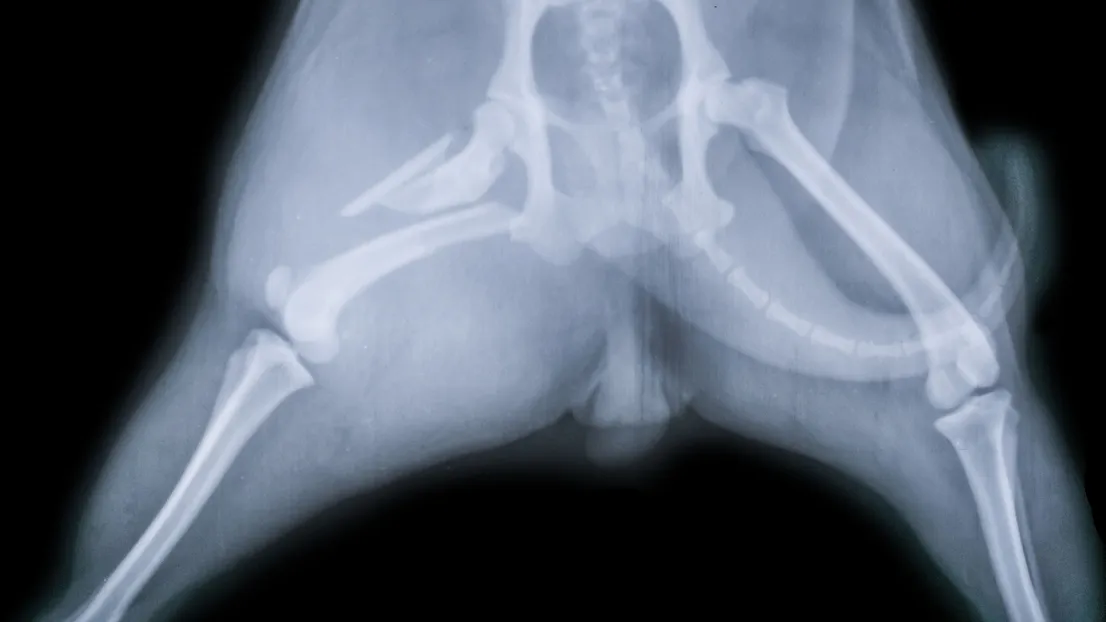

What is a Pet X-Ray?

A pet X-ray is a simple imaging test that lets veterinarians check for issues like broken bones, joint problems, or other health concerns. The process is usually quick, and most pets handle it without difficulty. The images give our veterinarians the information needed to provide the best care for your pet.